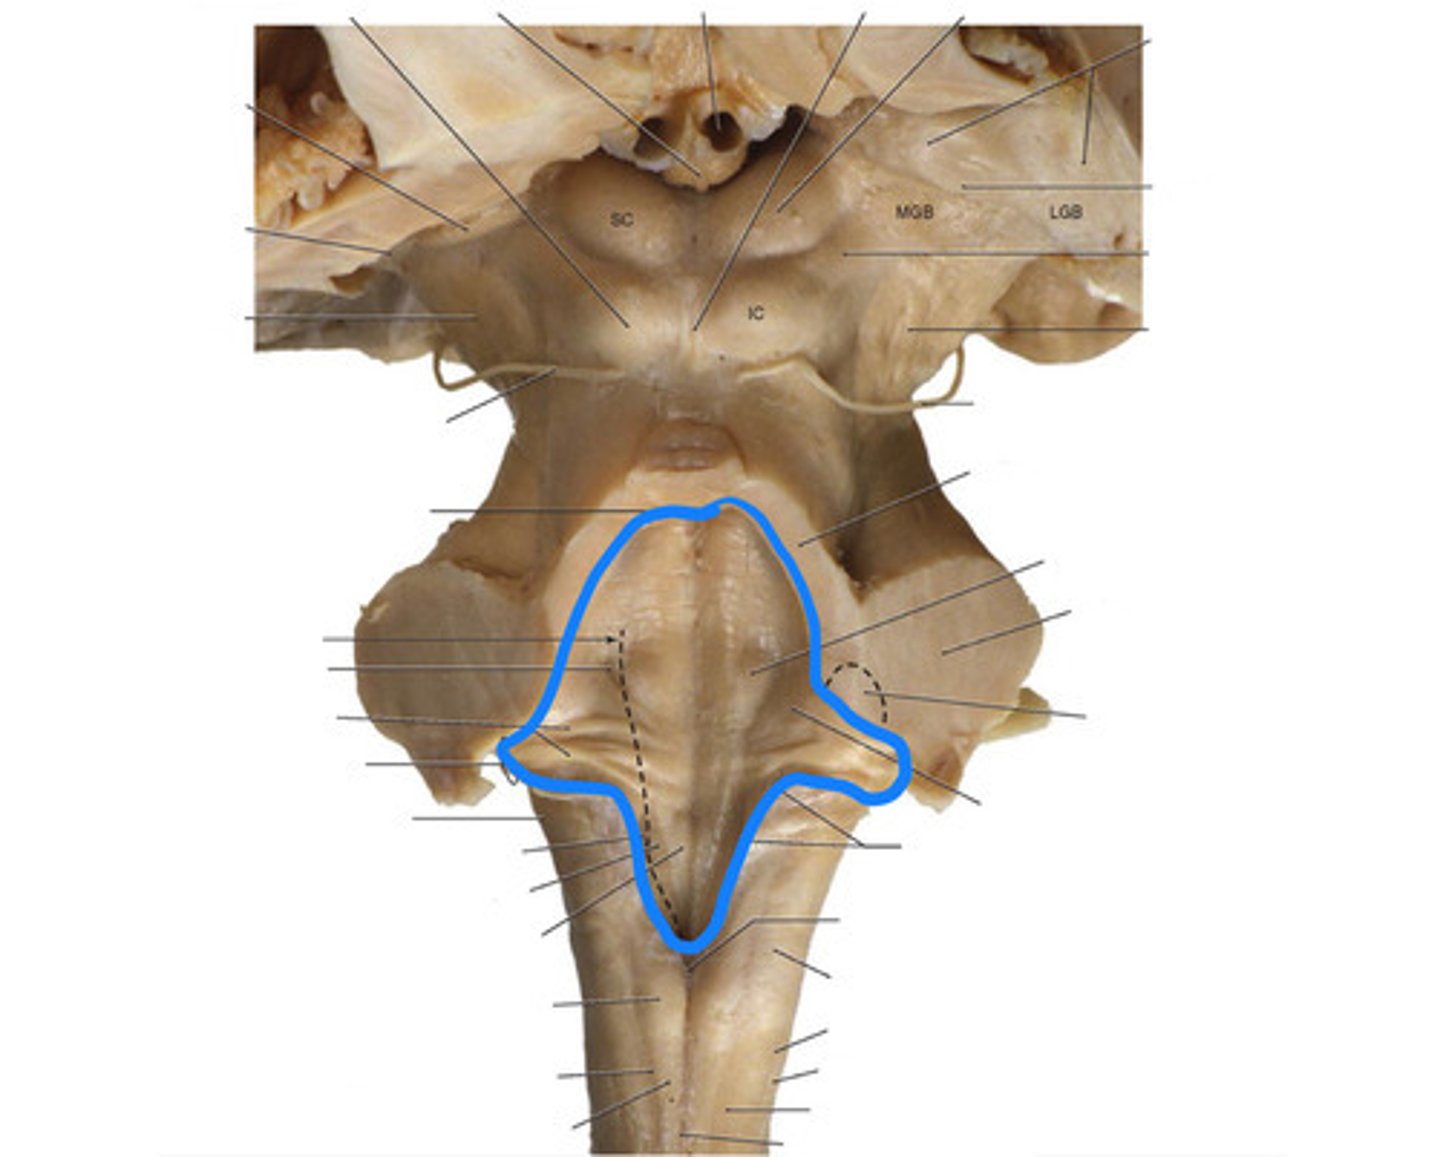

What anatomical aspect of the 4th ventricle is considered its floor?

rhomboid fossa

What forms the floor (rhomboid fossa) of the 4th ventricle?

dorsal surfaces of pons tegmentum and open medulla

inferior angle of the floor of the 4th ventricle

obex

vertical groove running in the floor of the 4th ventricle that separates it into right and left halves

dorsal median sulcus

vertical groove lateral to the dorsal median sulcus of the 4th ventricle

**same one that separated the alar and dorsal plates in the neural tube during development

sulcus limitans

refers to most of the floor of the 4th ventricle lateral to the sulcus limitans

**namesake nuclei are here

vestibular area

triangular region located in the caudal portion of the rhomboid fossa of the 4th ventricle, where the dorsal motor nucleus of CN X is

vagal trigone

Which parasympathetic nucleus is found in the vagal trigone of the 4th ventricle?

dorsal motor nucleus of X

triangular region located most medially in the caudal portion of the rhomboid fossa of the 4th ventricle, where the CN XII nucleus is

hypoglossal trigone

part of the 4th ventricle superior to the vagal and hypoglossal trigones (still medial to the sulcus limitans)

medial eminence

small bump located in the caudal portion of the medial eminence which forms from the motor fibers of CN VII as they wind around the underlying CN VI nucleus

facial colliculus

pigmented area that looks blue near the superior aspect of the sulcus limitans; cluster of noradrenergic cells

locus ceruleus

fibers that run horizontally in the central region of the rhomboid fossa of the 4th ventricle

stria medullares

area that helps to make the walls of the obex and is thought to be the "vomit trigger"

area postrema

floor of 4th ventricle

rhomboid fossa

sulcus limitans

floor of 4th ventricle lateral to sulcus limitans

vestibular area

vasal trigone

hypoglossal trigone

medial eminence

small bump in caudal portion of medial eminence

facial colliculus

stria medullares

A

superior cerebellar peduncles

superior medullary velum

inferior medullary velum